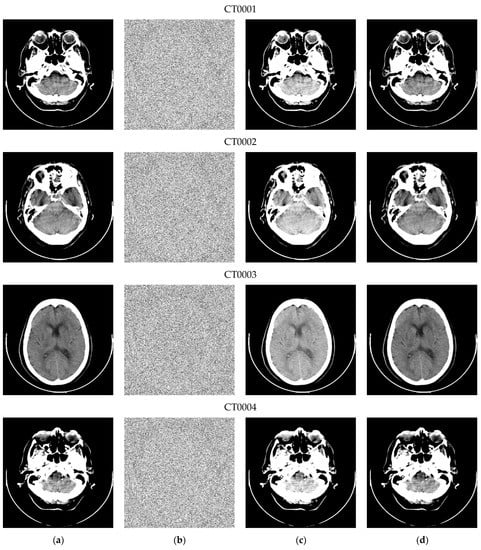

To demonstrate the correct operation of the developed scheme, the scheme was applied to 50 CT scans in grayscale, with dimensions of 512 × 512 pixels and a resolution of 12 bits/pixel, made up of pixels . The set of medical images, used in the experimentation, is mainly composed of skull images and was provided by the Mexican Institute of Social Security (IMSS). Some of these images and the results of the implementation are shown in Figure 12 and were visualized using the dedicated software of [31].

Figure 12.

Sample of (a) original CT scans, (b) encrypted versions with hidden data, (c) approximations, and (d) fully restored images. The images present embedding rates of 0.613, 0.654, 0.711, and 0.615 bpp, respectively.

Thanks to the design conditions of the proposed method, the implementation on medical images did not require any modification in the algorithm, but an adjustment of the encryption and embedding parameters. Considering that the CDM embedding was developed for images with a depth of eight bits/pixel, the first eight LSB planes were selected for data hiding, while the remaining four bit planes are considered MSB and encrypted with the AES-CTR algorithm, as indicated in Section 2.1. To perform the insertion of additional bits, the image is processed with a value of N ≤ 64; therefore, the product of the combinations of α and L should also not be greater than 64. Based on the experimental tests, it is recommended that the range of α values be [4, 16] to obtain a good ratio between capacity and imperceptibility.

As can be seen in Figure 12, the developed RDH-ED scheme is fully functional in digital imaging, in addition to generating approximate images with good visual quality, while allowing lossless data and image recovery. The capacity, PSNR, and SSIM values of the approximate images of CT0001, CT0002, CT0003, and CT0004 are (0.319 bpp, 74.961 dB, 0.999), (0.348 bpp, 74.916 dB, 0.999), (0.407 bpp, 47.77 bpp, 0.999), and (0.317 bpp, 74.972 dB, 0.999), respectively; parameters α = 5 and L = 2 were used to generate these images. More information on the performance of this implementation will be presented in the next section.